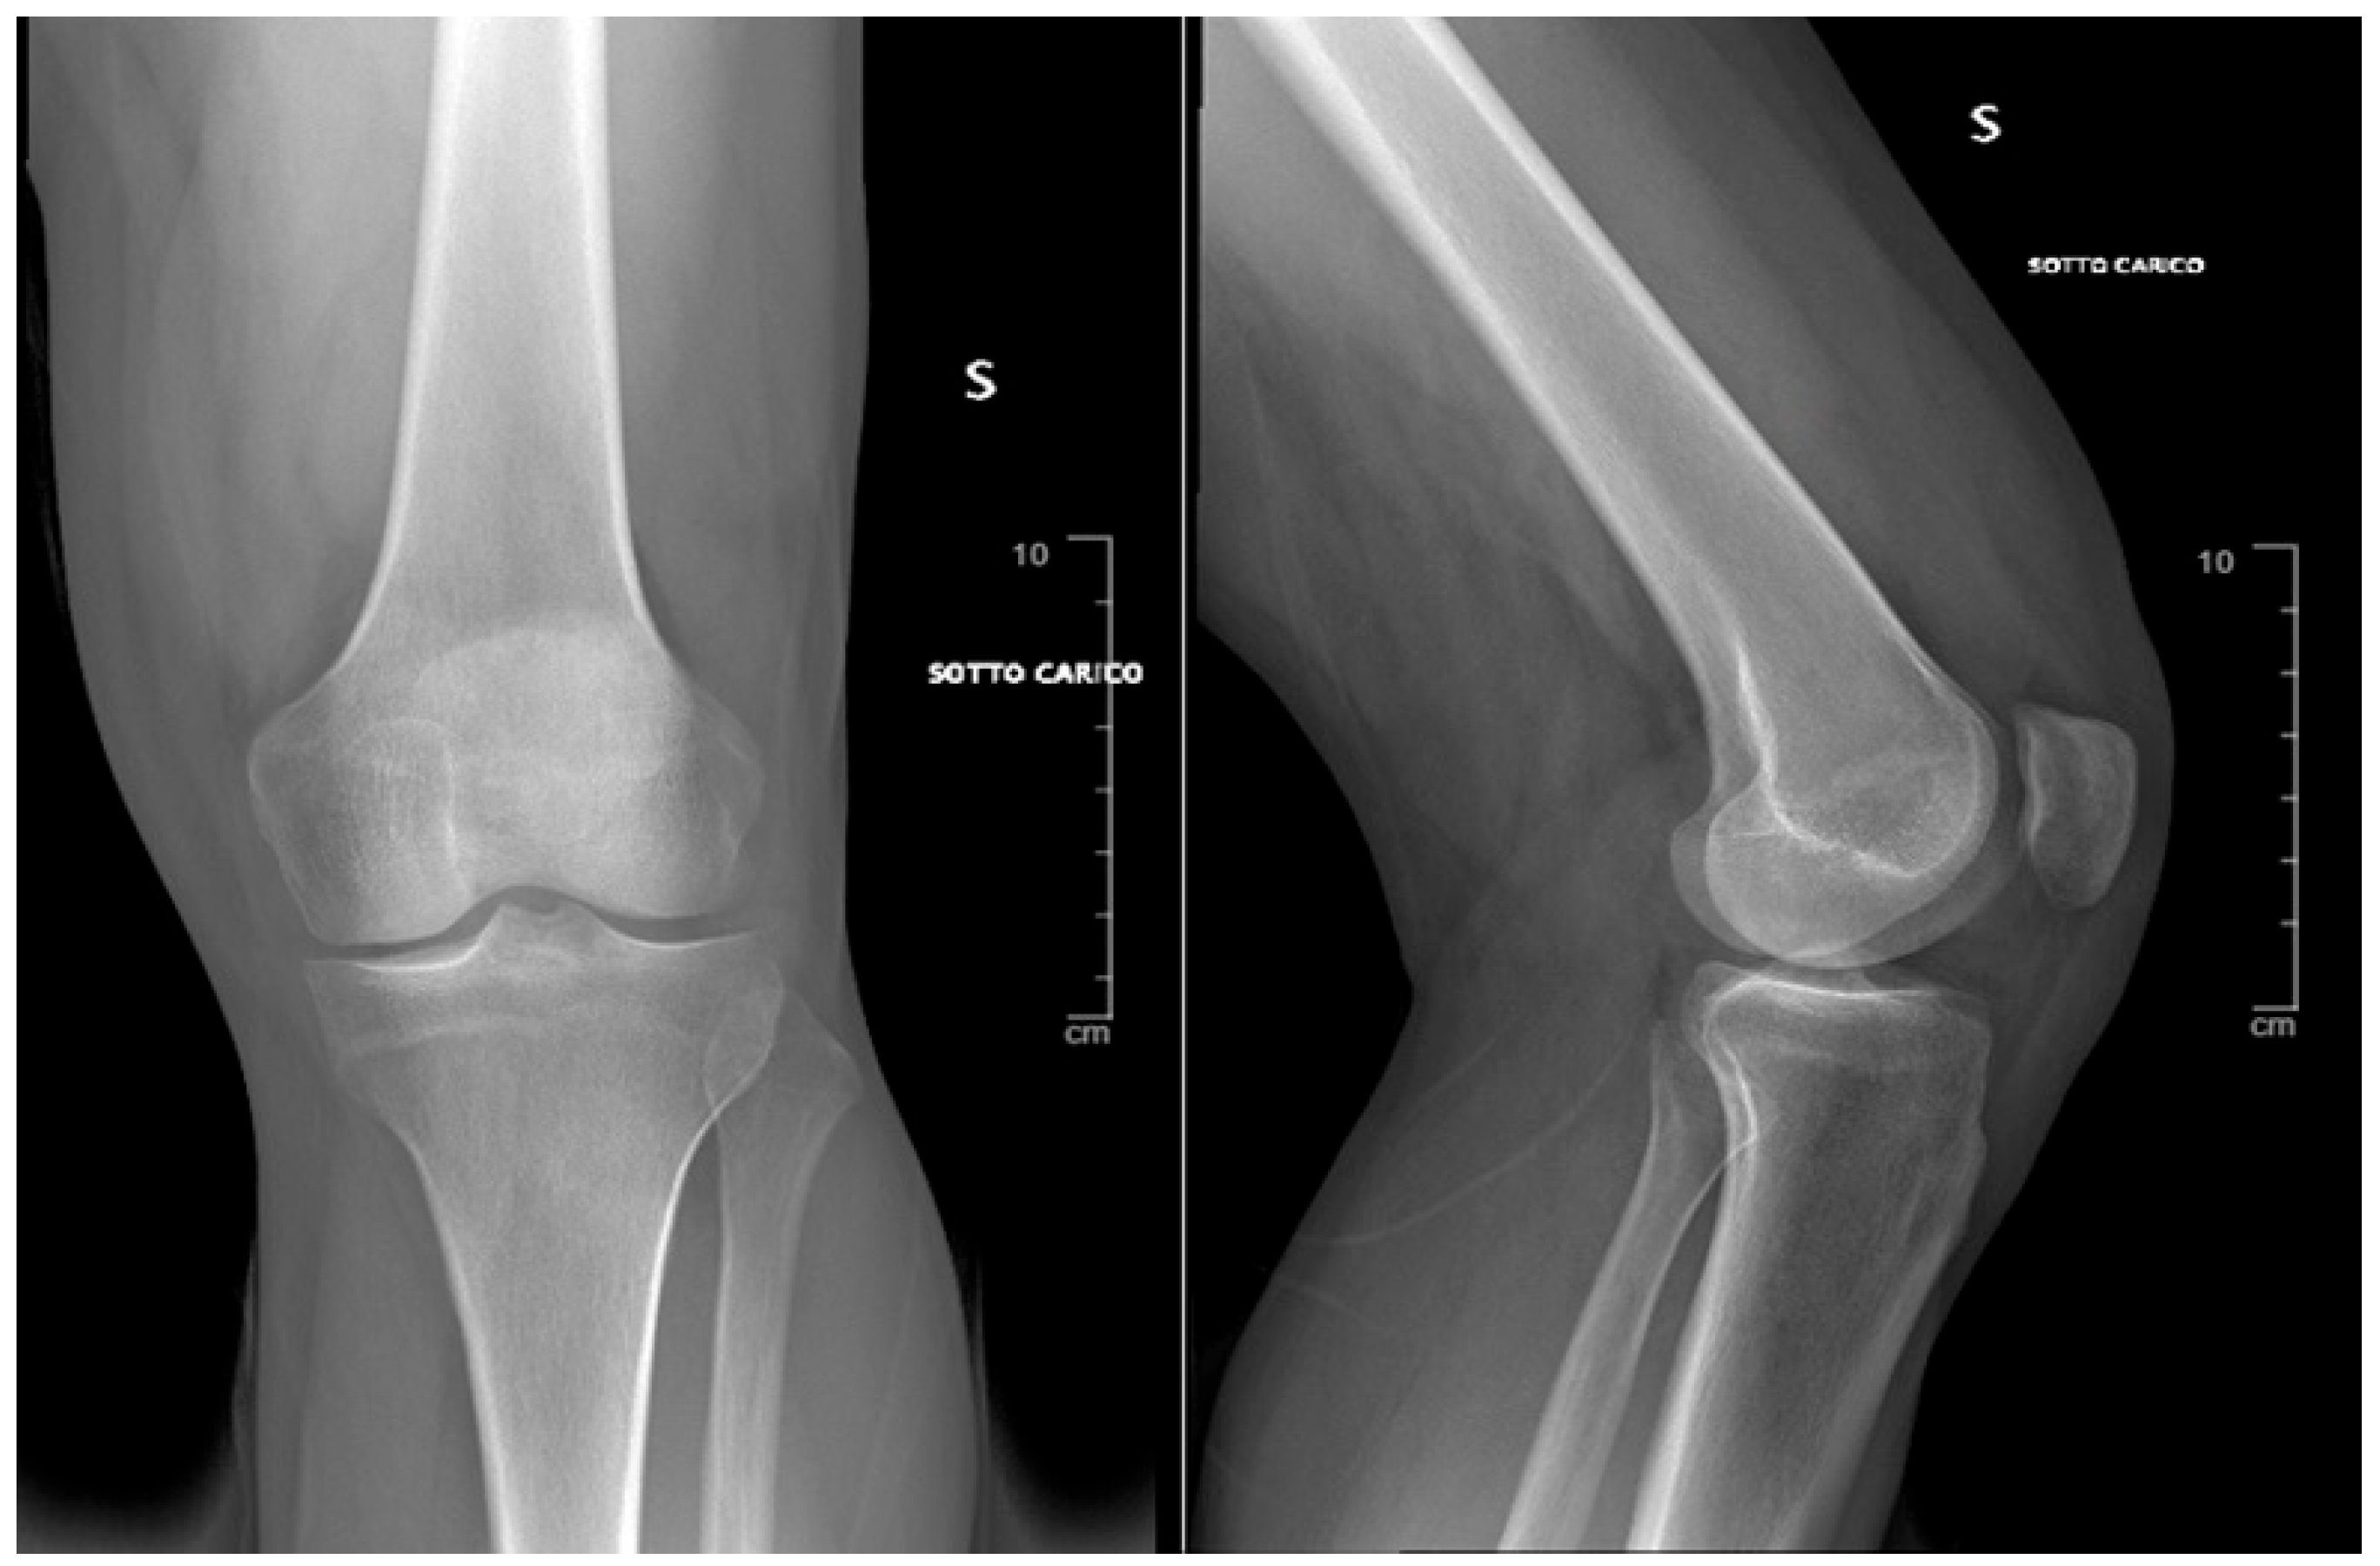

2. Case Presentation